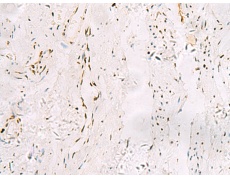

IHC positive control: |

Human esophagus cancer and Human cervical cancer |

IHC Recommend dilution: |

25-50 |